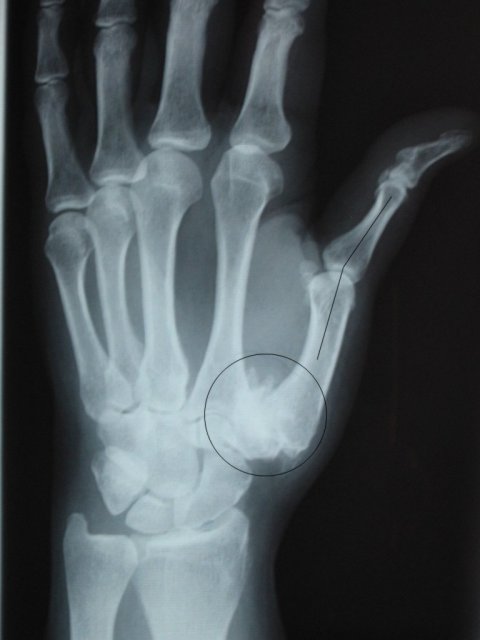

This is an x-ray of Betty Lou's left hand taken in 1985; normal at that time.

This x-ray reveals the recent damage. The circle highlights the affected area – most of the trapezium seems to have turned into sand. And the line shows how far the proximal phalange sometimes could move out of a normal position.